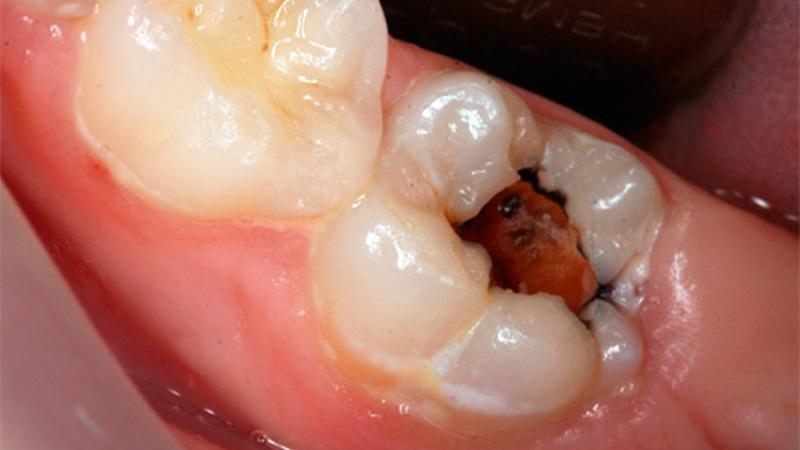

Хронический гипертрофический пульпит

Гипертрофический пульпит представляет собой серьезную форму заболевания. Его диагностика осуществляется при наличии следующих признаков:

- Сильные ноющие боли, которые, как правило, возникают при воздействии раздражителей. Также может наблюдаться кровоточивость в пораженной области во время жевания твердой пищи или при чистке зубов.

- Кариозный процесс обычно имеет выраженные проявления. Явное разрушение зуба становится заметным. Внутри зуба, пораженного кариесом, можно увидеть небольшое образование розоватого оттенка, указывающее на распространение воспалительного процесса.

- Неприятный запах изо рта часто сопровождает воспалительные процессы в ротовой полости. На некоторое время его можно устранить с помощью антисептических средств.

Лечение, как правило, проводится аналогично терапии острого пульпита. Важно помнить, что хроническая форма значительно отличается от острой, так как на определенных стадиях может вызывать серьезные негативные изменения в ротовой полости.